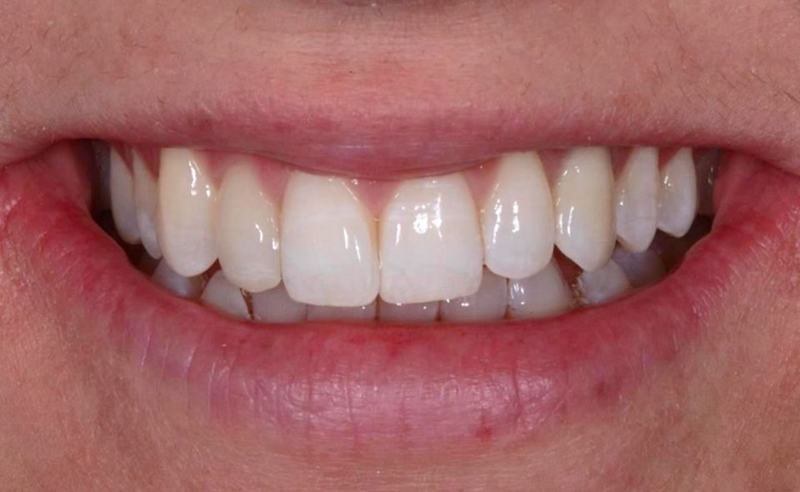

在这一点上,我们可以说我们满足了患者的所有需求和期望,并且与基线情况相比(图 64),我们可以看到一个很大的改进。

Fig. 64: Before and after the treatment: Note how the smile of the patient was improved simply by...

新的笑容和谐地融入了患者的脸上(图65-66),最后,她参与了每年一次随访的维护计划。

Fig. 65: The pleasant smile of the patient

Fig. 66: New smile is harmoniously integrated in the...